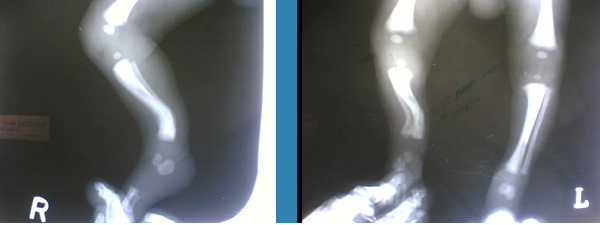

Spot diagnosis

What is the diagnosis?

Posteromedial tibial bowing. Tibial bowing specifically refers to bowing of the diaphysis of the tibia with the apex of the deformity directed anterolaterally, anteromedially, or posteromedially. Anterolateral bowing is associated with pseudarthrosis of the tibia and neurofibromatosis. Anteromedial bowing is associated with fibular hemimelia. Posteromedial bowing is a congenital bowing of the tibia {with the apex directed posteriorly and medially} and a calcaneovalgus foot deformity. Both of these deformities tend to resolve with little clinical disability` however, a leg-length inequality commonly develops that often requires treatment. Initial treatment of the tibial bowing foot deformity includes stretching, serial casting, or splinting. The bowing deformity rapidly corrects. A 50 percent correction is usually seen by age 2 years, although a mild deformity often persists.